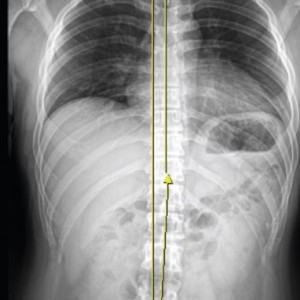

[ 척추 X 어깨 X 골반 X 족부 복합 치료 ]

01.

척추

척추측만증 또는 좌, 우 한쪽으로 기울어진 척추로 인해 체중이 한쪽 허리로 집중된다면 장기적으로 체중이 기울어진 쪽 허리에 뼈가 자라거나 퇴행성 변화가 빠르게 진행됩니다.

02.

어깨

목이 한쪽으로 기울거나 한쪽 어깨가 반대쪽에 비해 낮다면 상체의 무게가 한쪽 허리로 쏠리게 됩니다. 이때 낮은 쪽의 어깨는 광배근에 의해 허리로 연결되므로 어깨 높이 차이는 좌우 허리 근육의 불균형을 유발하여 허리 통증을 악화시킵니다.

03.

골반

허리는 골반위에 수직으로 서 있는 구조물이기 때문에 골반의 틀어짐은 필연적으로 허리를 틀어지게 만들어 허리에 많은 스트레스를 유발합니다. 만약 골반이 뒤로 기울어진 골반후방경사가 있다면 디스크탈출증을 더욱 악화시키며, 한쪽으로 회전되고 기울어진 골반은 체중이 집중되어 허리디스크와 협착증을 악화시키기 때문에 골반교정은 매우 중요합니다.